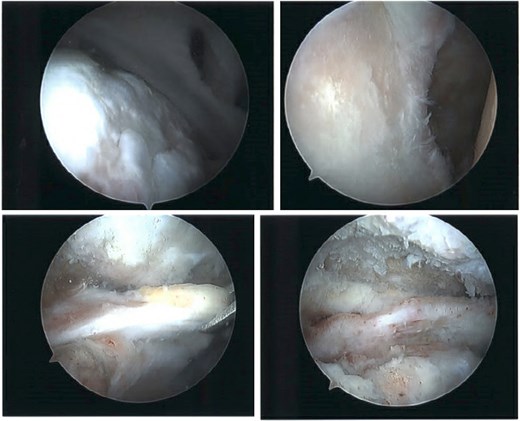

The patient was determined to be a candidate for surgical intervention given his age, ongoing symptoms, and continued dysfunction. Expectations of surgical treatment were discussed, including the possibility of a less reliable outcome regarding his right shoulder given his previous surgical history. Six weeks after injury, the patient underwent left shoulder rotator cuff arthroscopic repair. Findings included full-thickness tears of the subscapularis, supraspinatus, and infraspinatus, with glenohumeral chondromalacia (Fig. 7). He was maintained in a Frank Stubbs immobilizer for 6 weeks and then started physical therapy.

Intraoperative imaging of left shoulder arthroscopic debridement and rotator cuff repair including findings of full-thickness supraspinatus and subscapularis tendon tears, which subsequently were repaired.

The patient continued to experience right shoulder disability, including pain, limited range of motion, and sleep disturbance. Operative intervention was delayed due to elevated liver enzymes, attributed to chronic acetaminophen use; he underwent right shoulder arthroscopy ~9 months after injury. Intraoperative findings confirmed extensive, irreparable tearing of the supraspinatus and infraspinatus, glenohumeral degenerative change, and deficient biceps tendon (Fig. 8). The joint was debrided and staged reverse total shoulder arthroplasty (rTSA) was discussed.

Intraoperative imaging of right shoulder arthroscopic debridement including findings of full-thickness supraspinatus and subscapularis tendon tears, which subsequently were not able to be repaired, as well as significant glenohumeral degenerative change.